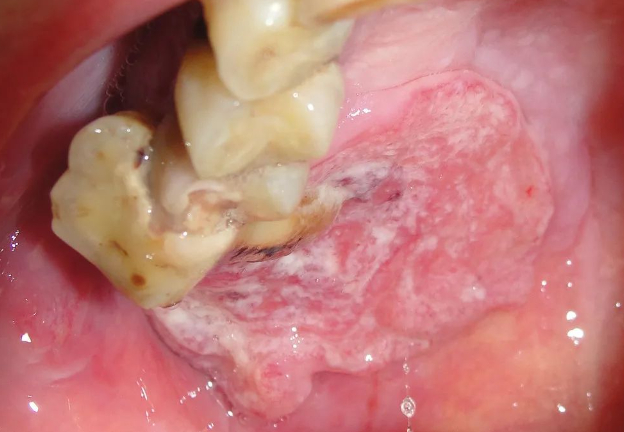

口腔癌主要发生在中老年人,一般男性多于女性,多为鳞状细胞癌。根据在口腔黏膜的发病部位不同,可以分为唇癌、舌癌和颊癌等。口腔癌如果发现不及时,容易转移到颈淋巴结或肺等全身多处器官。

上腭口腔鳞状细胞癌。